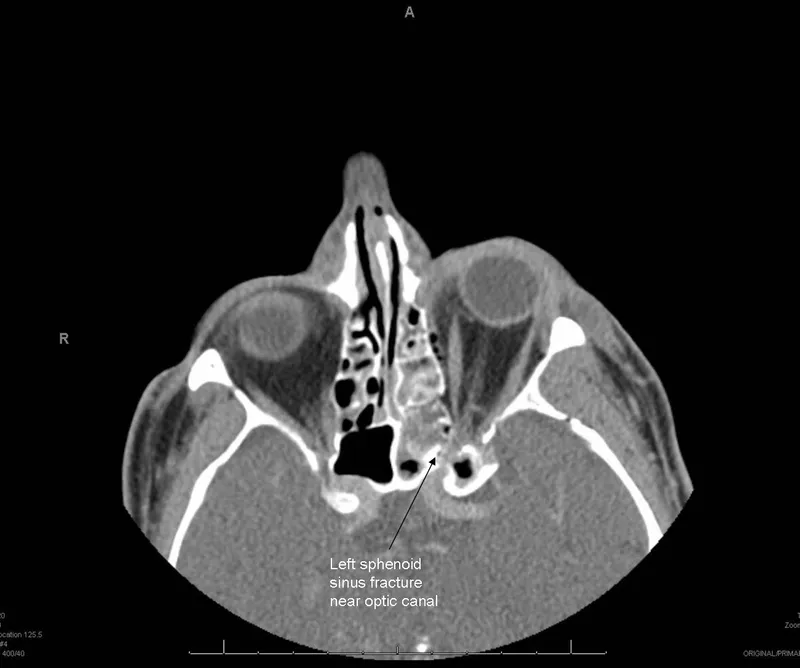

Traumatic Optic Neuropathy - Impact Insights

Classification:

- Direct TON: Penetrating injury, foreign body, direct nerve trauma.

- Indirect TON: More common; blunt head trauma (e.g., frontal impact). Forces transmitted to optic canal.

Pathophysiology (Indirect): Shearing forces on nerve fibers, vascular compromise (ischemia), edema within the unyielding optic canal.

Clinical Presentation: Acute, often severe, unilateral vision loss; Relative Afferent Pupillary Defect (RAPD) prominent; dyschromatopsia, visual field defects.

Immediate Assessment: Visual acuity, pupillary reactions, fundoscopy (may be normal initially), high-resolution CT scan (thin cuts of optic canal for fractures).

Management (Indirect TON): Highly controversial; evidence for any intervention is limited.

Options include observation, high-dose corticosteroids, or surgical optic nerve decompression. Decision is individualized.

⭐ The use of high-dose corticosteroids in indirect Traumatic Optic Neuropathy (TON) is controversial and not universally recommended; management decisions are often individualized based on presentation and timing.